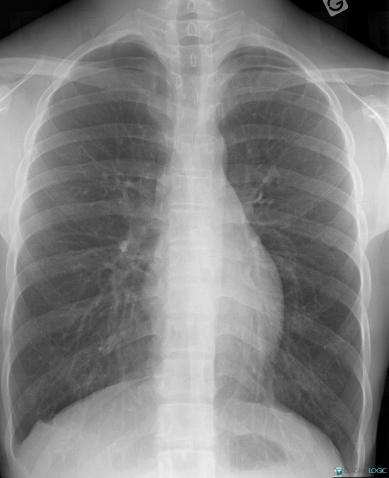

Pneumothorax, Plèvre, Radio

Voici les informations spécifiques à l'image clé ci dessus:

- Diagnostic Pneumothorax, Localisation(s) Plèvre, comportant les gammes